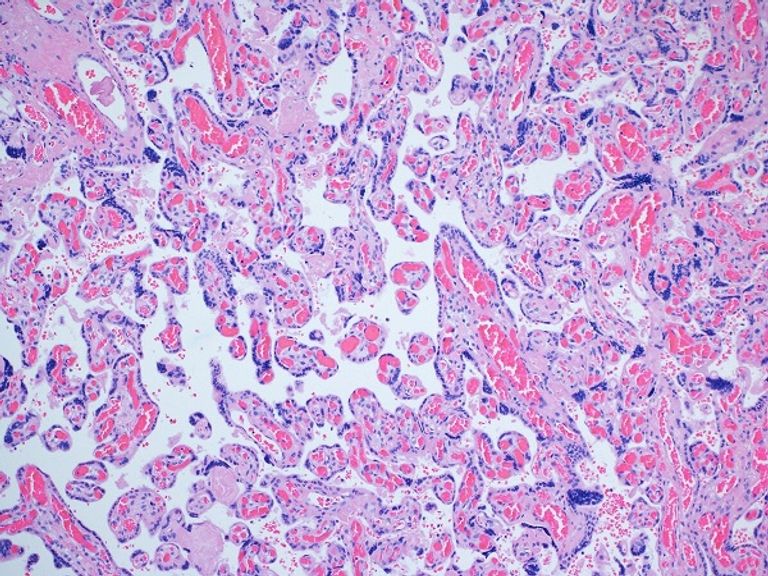

وجمع مؤلفو الدراسة مشيمة من 84 مريضة تم تطعيمهن و116 مريضة غير محصنة تمت ولادتهن في مستشفى برنتيس للنساء في شيكاغو وفحصوا المشيمة بشكل مرضي وبعد الولادة مجهريًا، وتلقى معظم المرضى لقاحات - إما موديرنا أو فايزر - خلال الثلث الثالث من الحمل.

وفي مايو/ أيار الماضي، نشر جولدشتاين وميلر ومتعاونون من مستشفى نورث وسترن وآن وروبرت إتش لوري للأطفال في شيكاغو، دراسة وجدت أن مشيمة النساء اللائي ثبتت إصابتهن بفيروس (كوفيد -19) أثناء الحمل أظهرن دليلًا على الإصابة.

والمشيمة هي أول عضو يتشكل أثناء الحمل، ويقوم بأداء مهام لمعظم أعضاء الجنين أثناء تكوّنها، مثل توفير الأكسجين أثناء نمو الرئتين والتغذية أثناء تكوّن القناة الهضمية.

بالإضافة إلى ذلك، تدير المشيمة الهرمونات والجهاز المناعي، وتطلب من جسم الأم الترحيب بالجنين ورعايته بدلاً من رفضه باعتباره دخيلًا أجنبيًا.